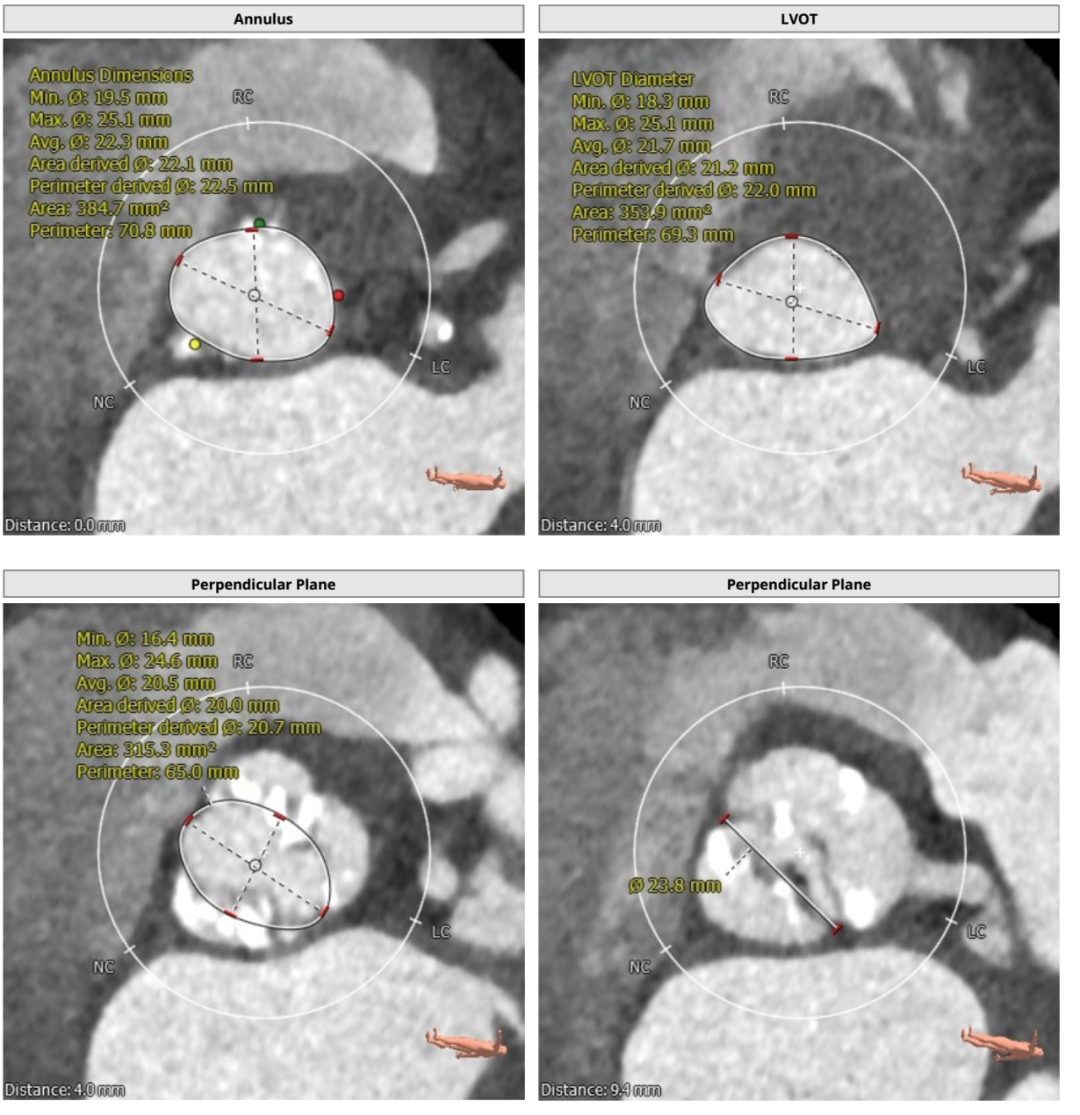

根部解刨: